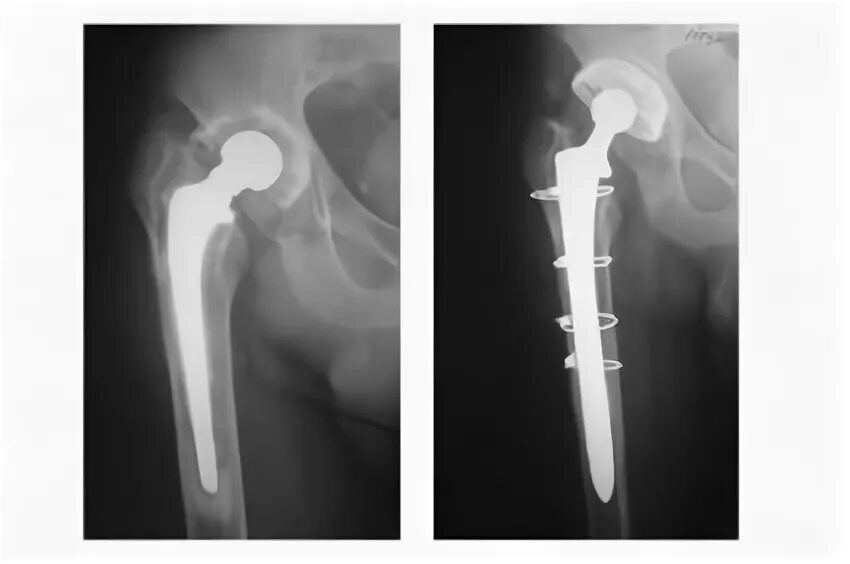

Расшатывание эндопротеза тазобедренного сустава